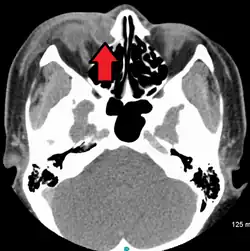

| A case of dacryocystitis as seen on CT scan | |

Dacryocystitis is an infection of the lacrimal sac, secondary to obstruction of the nasolacrimal duct at the junction of the lacrimal sac.[1] The term derives from Greek dákryon 'tear' cysta 'sac' and -itis 'inflammation'.[2] It causes pain, redness, and swelling over the inner aspect of the lower eyelid and epiphora. When nasolacrimal duct obstruction is secondary to a congenital barrier it is referred to as dacryocystocele. It is most commonly caused by Staphylococcus aureus and Streptococcus pneumoniae.[3] The most common complication is corneal ulceration, frequently in association with S. pneumoniae.[3] The mainstays of treatment are oral antibiotics, warm compresses, and relief of nasolacrimal duct obstruction by dacryocystorhinostomy.[3]